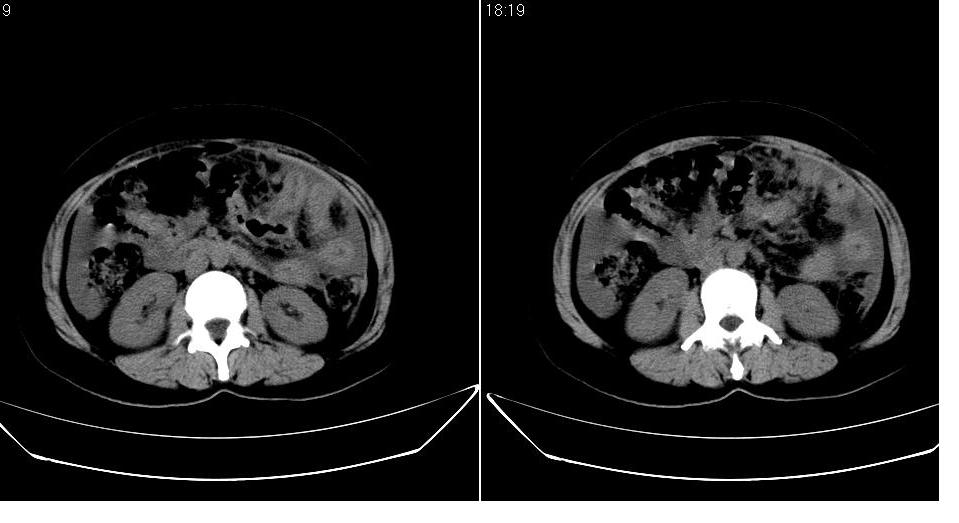

以下是引用zbp537在2009-1-19 14:09:00的发言:[br]从这个平扫图像上看,只能考虑:1、胸腹水。2、脾脏包膜下弧形高密度影,疑出血,建议复查。[br]既然腹水中有恶性细胞,建议行腹部ct增强扫描及胸部扫描。

以下是引用随光逐影在2009-1-19 15:47:00的发言:[br]1)不排除胃癌可能;建议行胃镜检查。2)腹水。3)右侧胸腔积液。

以下是引用jiangjing在2009-1-19 18:21:00的发言:[br]1 网膜污垢征---肿瘤网膜转移.2)腹水。3)右侧胸腔积液